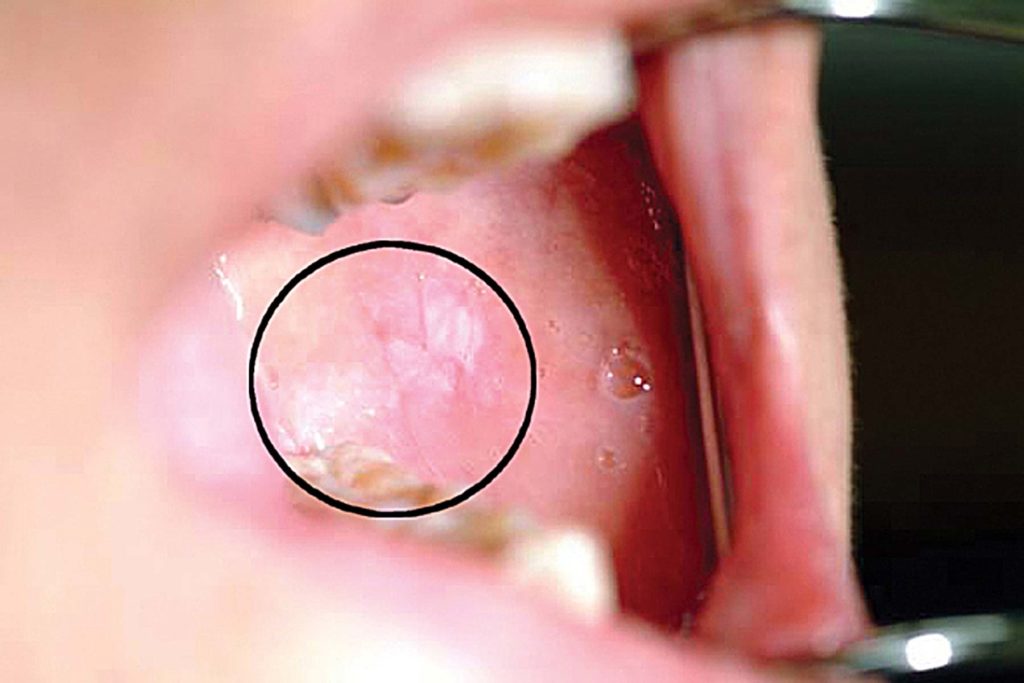

Take this quiz to discover whether you might be suffering from mouth cancer. Click the card to flip 👆. Oral cancer screening is an examination performed by a dentist or doctor to look for signs of cancer or precancerous. Yearly screenings are recommended as early. Click the card to flip. Your doctor or dentist will examine your lips. Oral cancer, also called mouth cancer, forms in the oral cavity, which includes all parts of your mouth that you can see if you. In 2015 we launched a simple head and neck cancer check which can be carried out by anyone at home, at any time, but ideally once per month. The primary screening test for oral cancer is a clinical exam of the mouth. Oral and pharyngeal cancer , due to squamous cell carcinoma.

Mouth Cancer Quiz In 2015 we launched a simple head and neck cancer check which can be carried out by anyone at home, at any time, but ideally once per month. Oral and pharyngeal cancer , due to squamous cell carcinoma. Tests and procedures used to diagnose mouth cancer include: What is cancer of the oral cavity? In 2015 we launched a simple head and neck cancer check which can be carried out by anyone at home, at any time, but ideally once per month. Learn about the symptoms and signs of this serious condition. Your doctor or dentist will examine your lips. Click the card to flip 👆. Oral cancer, also called mouth cancer, forms in the oral cavity, which includes all parts of your mouth that you can see if you. Take this quiz to discover whether you might be suffering from mouth cancer. Click the card to flip. Yearly screenings are recommended as early. The primary screening test for oral cancer is a clinical exam of the mouth. Oral cancer screening is an examination performed by a dentist or doctor to look for signs of cancer or precancerous.